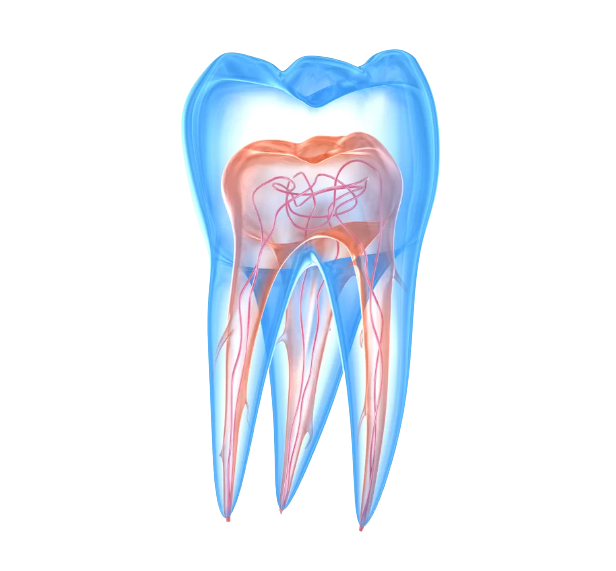

Lors de la première consultation, nous prenons tout le temps nécessaire pour obtenir une image complète de votre santé bucco-dentaire. Pour ce faire, nous procédons à un examen approfondi, au cours duquel nous recherchons notamment d'éventuelles inflammations ou autres problèmes aigus.

Pour ce faire, nous réalisons des radiographies (si nécessaire), des photos couleur et toujours des modèles numériques 3D de votre dentition. Nous examinons vos dents, vos gencives et vos muqueuses afin de détecter à temps toute anomalie ou maladie. Nous vérifions également la couleur et la position de vos dents.

Hygiène bucco-dentaire/parodontologie : pour des gencives saines et une bouche propre.

Dentisterie générale : comme les obturations et autres traitements de base.

Restauration fonctionnelle : restauration de la fonction masticatoire, remplacement des dents perdues et traitement de l'usure.